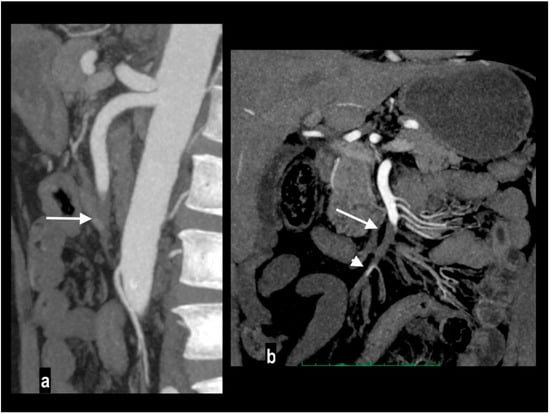

Embolic disease is usually a manifestation of underlying cardiovascular disease [42] (atrial fibrillation, endocarditis) or, less frequently, aortic or mesenteric plaques, and it usually involves a high-flow SMA due to the narrow take-off angle from the aorta [2]. The topography and extent of the involved segment depend on the location of the embolus (Figure 2): the inflow to the proximal jejunum is preserved if the embolus is located near the takeoff of the middle colic artery, sparing inferior pancreaticoduodenal branches, or almost complete ischemia of the small intestine occurs if the embolus is located close to the SMA orifice [2,39,43,44].

Figure 2.

Embolic mesenteric ischemia in a 57-year-old man with atrial fibrillation. Coronal MIP arterial image (a) showed embolic occlusion of middle SMA (arrow), with preserved jejunal arteries enhancement and right colonic vessels collateralization. Hypoenhancing wall was appreciated only in distal ileus ((b) arrows).

Involved vascular beds are usually healthy and show poor collateralization, so clinical presentation and evolution to transmural necrosis occur earlier; moreover, concurrent emboli can involve other splanchnic arteries, particularly renal and splenic ones, determining parenchymal infarcts (Figure 3).

Figure 3.

Acute abdominal pain in a 52-year-old with atrial fibrillation. Oblique sagittal and coronal MIP arterial images showed embolic occlusion of the middle SMA (arrow), with subtle peripheral segmentary enhancement of distal lumen (arrowhead) by a collateral vessel (a,b). Hypoenhancing ileal (arrow) and right colon (arrowheads) walls were well appreciated in comparison to jejunal loops (circle) on left abdominal side (c). A left renal infarct (arrow) was also present (d). Patient underwent a right colectomy.